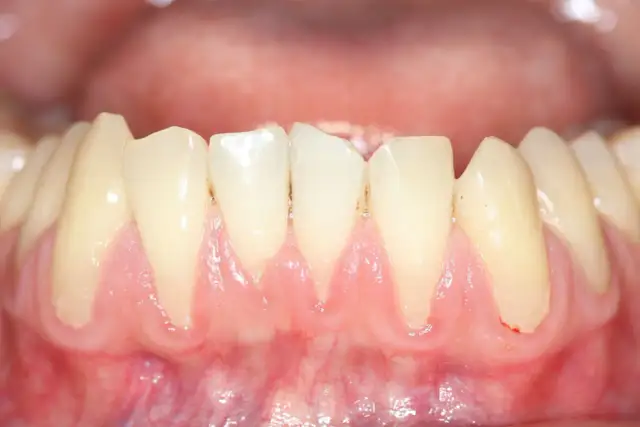

Paradontoza: Kiedy wypadają zęby? Czy da się je uratować?

Paradontoza: Kiedy zęby wypadają? Poznaj objawy zaawansowanej choroby i skuteczne metody leczenia, by uratować swój uśmiech. Sprawdź, co możesz zrobić!